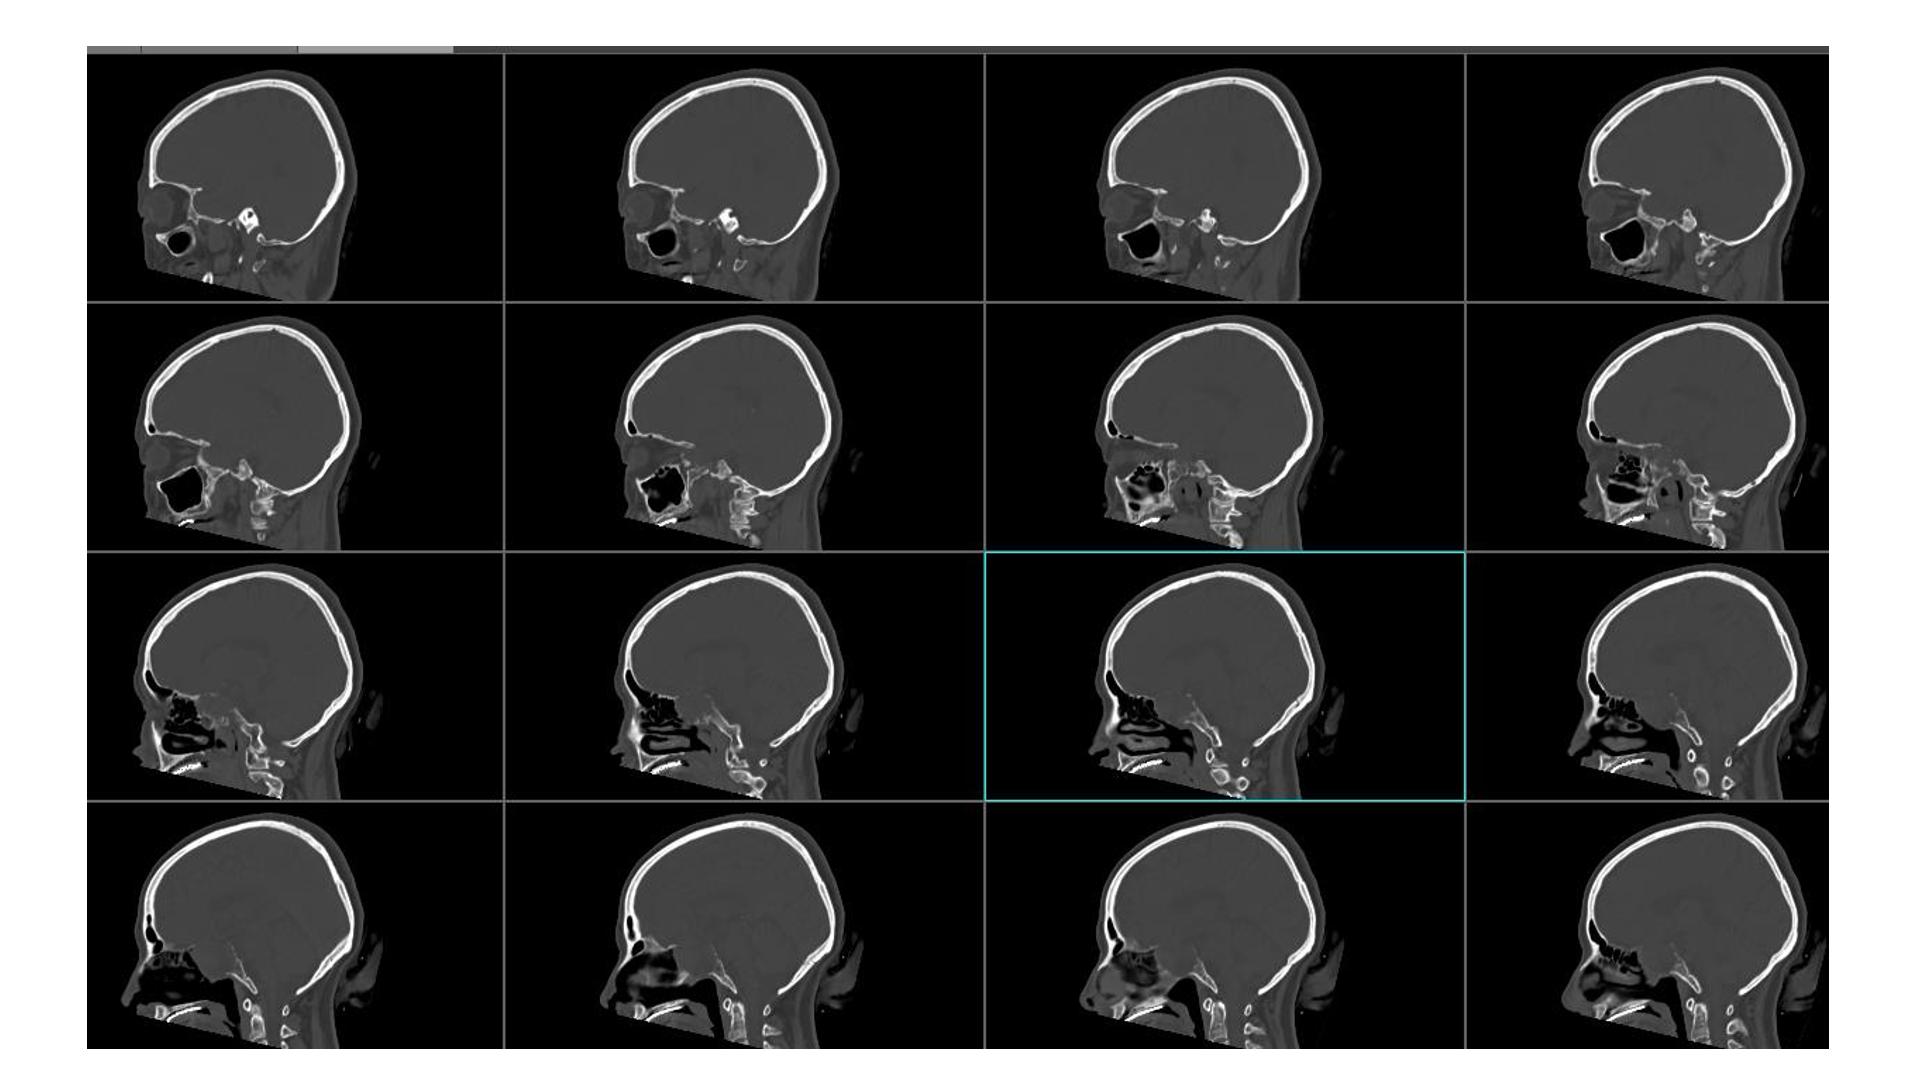

鞍区占位,蝶鞍扩大明显,侵袭海绵窦。